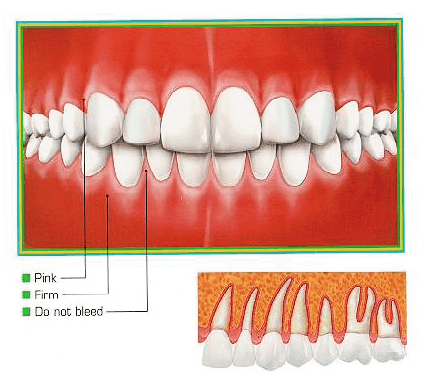

치주질환이 없는 건강한 잇몸은 출혈이 되지 않으며 골소실이 없다